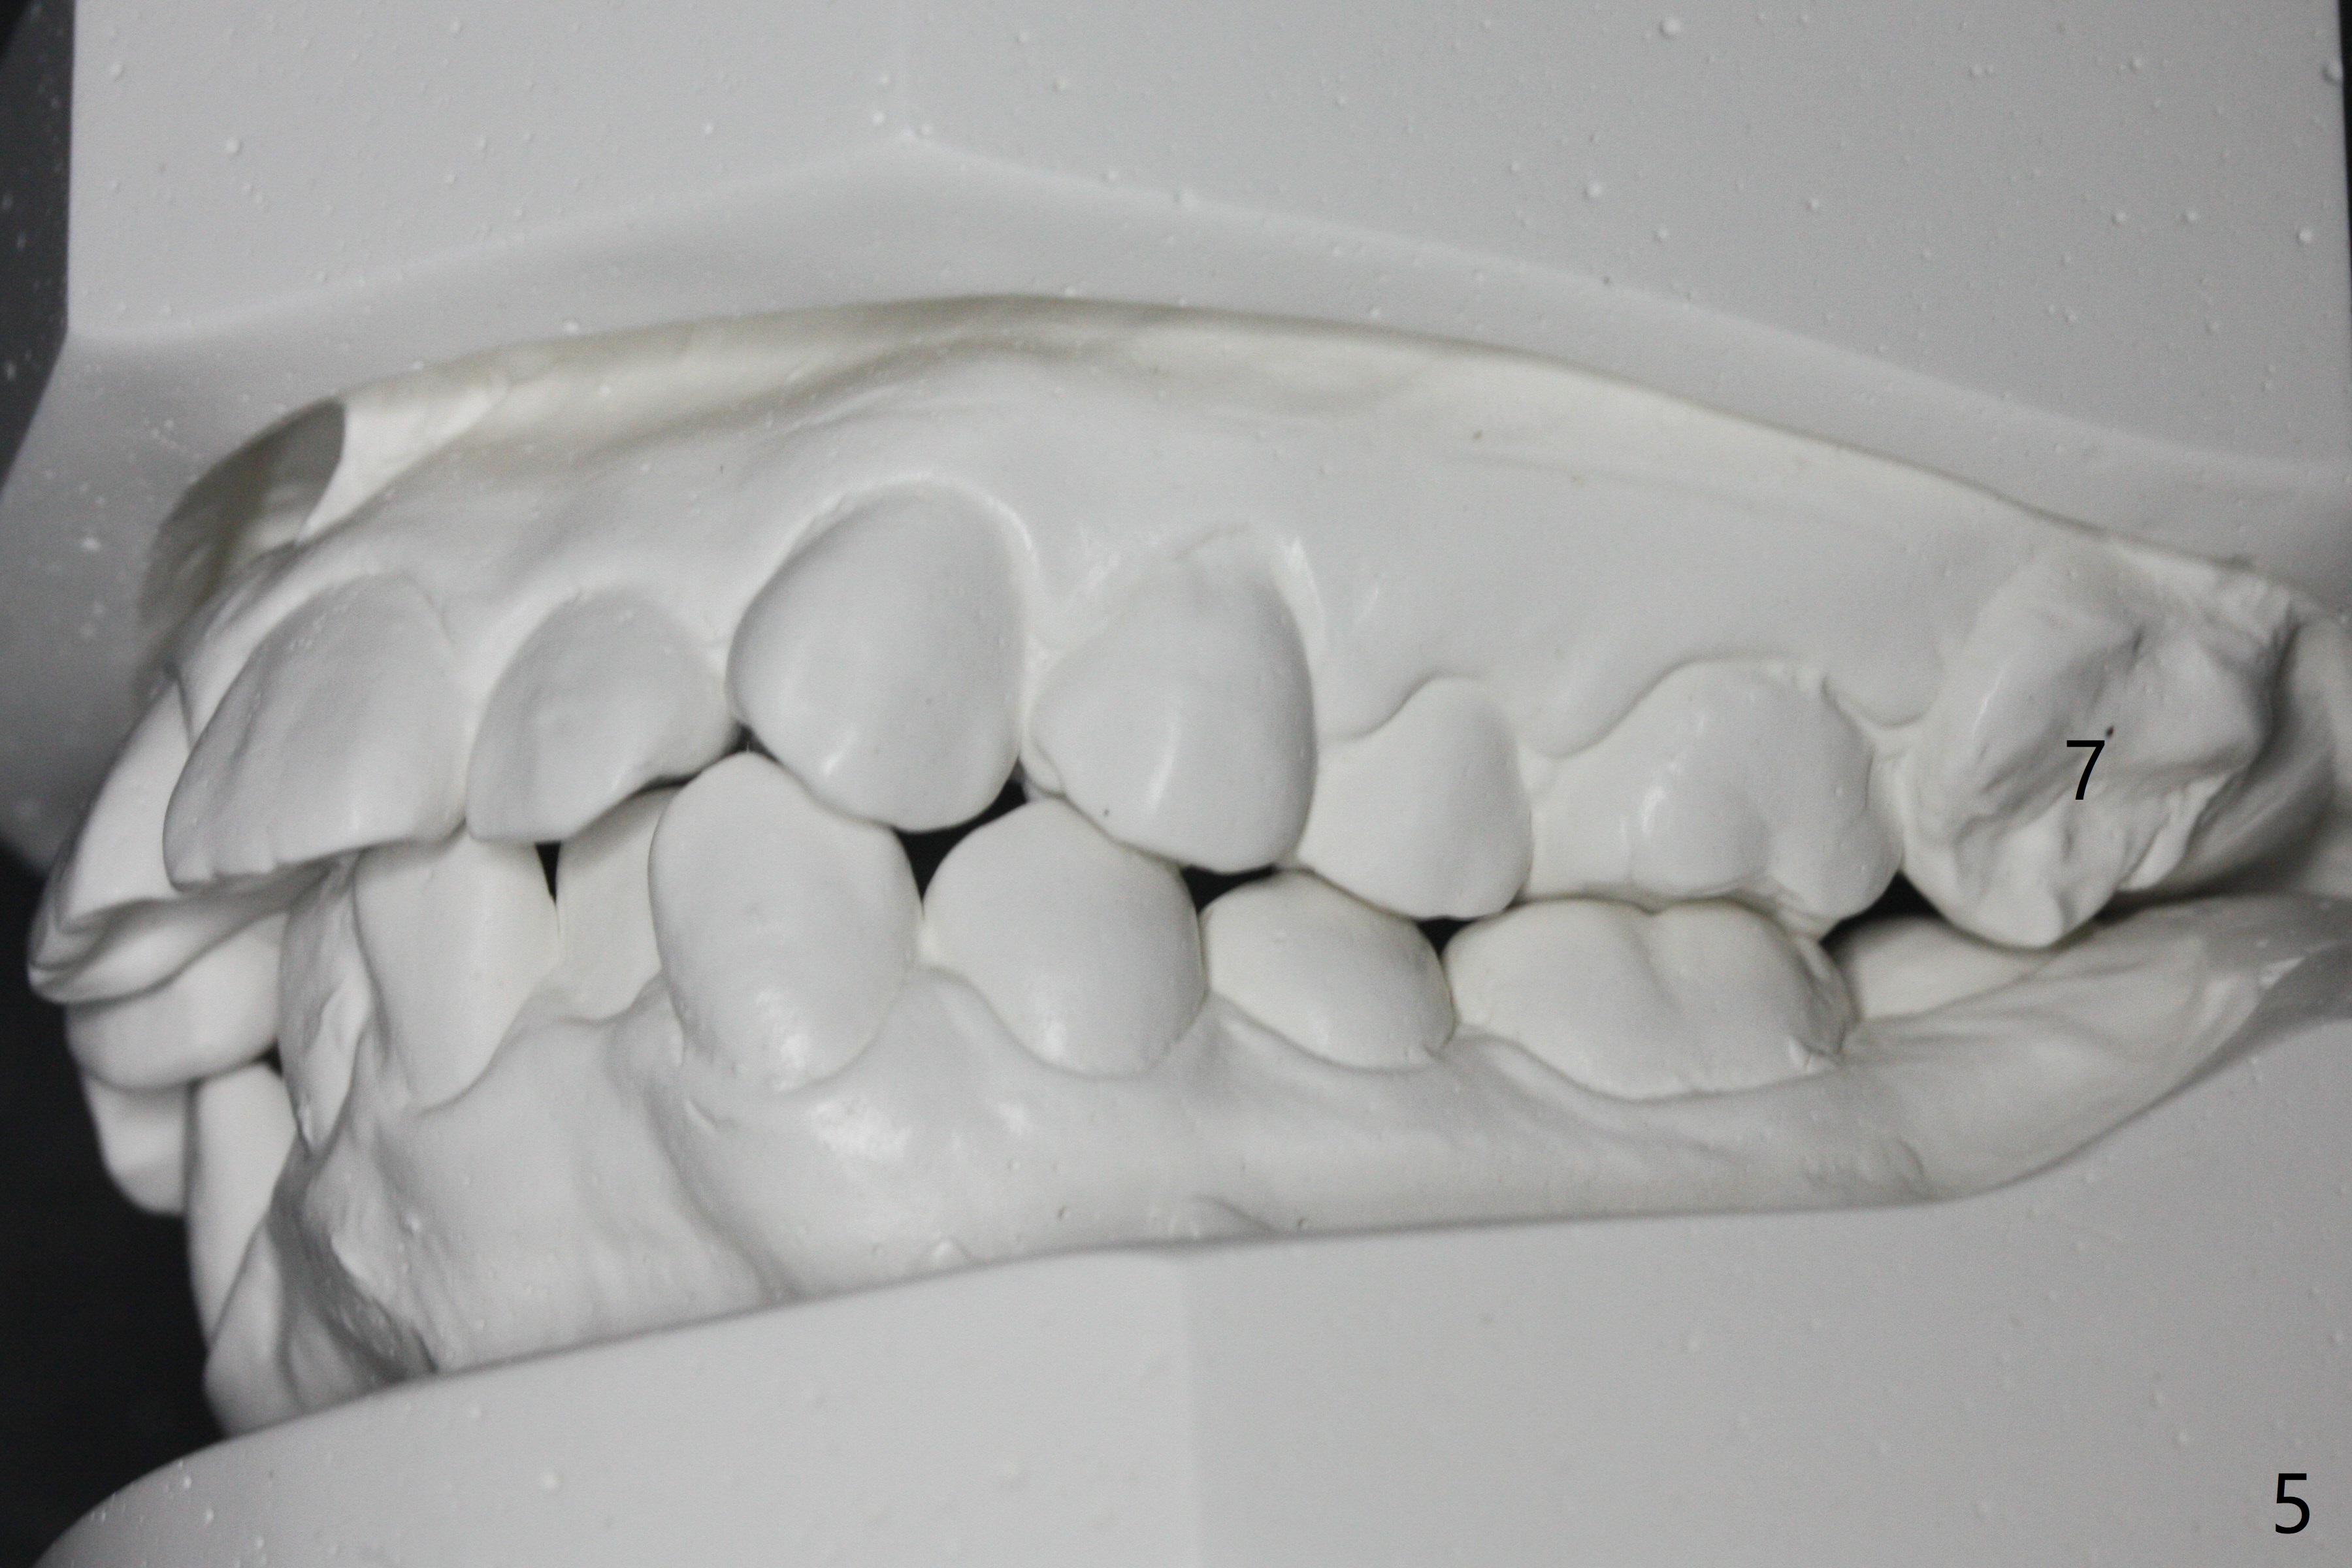

A 17-year-old woman has protrusive lips (Fig.1,2). Due to severe crowding (Fig.3-5), four of the 1st bicuspids are extracted prior to separator placement. It appears that spaces are easier to open up with extraction first. Choose 2nd molar bands with lingual cleats so that 2nd molar cross bite will be corrected immediately post banding (Fig.4,5). Place composite in the occlusal surface of the 1st molars for occlusal separation. Because of severe rotation of UR2, do not place bracket. The same can be applied to L2s. Place power chains x 4 between L3 and 6. The same mechanic will be applied to the right side when R5s are buccalized. Occlusal composite needs to be built up high and several times because of frequent wear, fracturing or detachment (Fig.6 * (1.5 months post banding)).

Three months post banding, the cross bite at 7s is corrected; with 7s' supraeruption and 6s' infraocclusion (because of occlusal composite (just removed), Fig.7,8), anterior open bite occur. Next visit place brackets in L7s with flexible wire. While 2 mechanisms are applied to gain more space for LR2 (Fig.9 *, ^), a special mechanism is utilized to correct LL2 cross bite (space gained). If the space for UR2 (Fig.10) is insufficient next appointment, what should we do? Otherwise, what should be done?